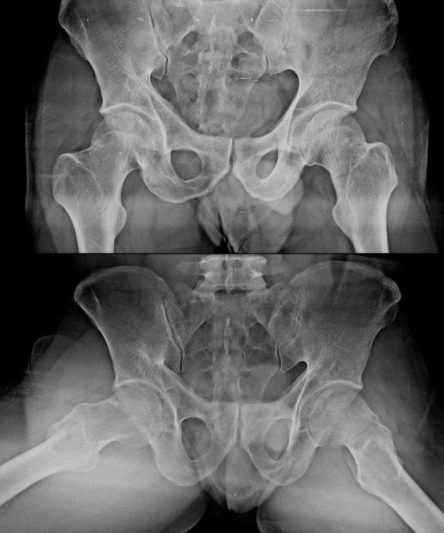

Microskan with Ultra high frequency can take the Lateral Lumbar Spine image of a 90 kg Patient with the correct image receptor